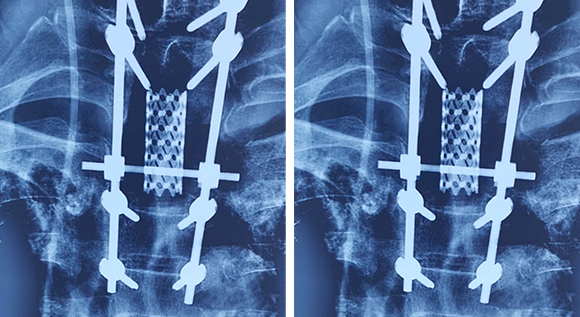

脊柱脊髓神經(jīng)微創(chuàng)中心以微創(chuàng)技術(shù)為引領(lǐng),以功能恢復(fù)為目標(biāo),主要治療脊柱外傷、腫瘤、退行性病變、脊柱畸形等疾病。團(tuán)隊(duì)利用神經(jīng)外科顯微技術(shù),結(jié)合神經(jīng)內(nèi)鏡微創(chuàng)技術(shù),對(duì)脊柱間盤變性疾病、頸腰椎管狹窄、頸腰椎間孔狹窄、頸腰椎間盤突出、頸腰椎體不穩(wěn)、脊柱骨折、寰樞椎脫位、脊柱腫瘤、椎管內(nèi)腫瘤、脊髓損傷、脊髓空洞、脊髓栓系等疾病進(jìn)行高效、特色手術(shù)治療,如顱頸交界區(qū)畸形寰枕減壓內(nèi)固定術(shù)、脊柱腫瘤全脊椎切除內(nèi)固定術(shù)、微創(chuàng)椎管內(nèi)腫瘤切除術(shù)、微創(chuàng)脊柱旁腫瘤切除術(shù)、寰樞椎脫位椎間融合內(nèi)固定術(shù)、脊柱骨折微創(chuàng)經(jīng)皮椎弓根釘內(nèi)固定術(shù)、經(jīng)椎間孔椎間融合內(nèi)固定術(shù)(MIS—TLIF)等,最大程度降低脊柱脊髓手術(shù)創(chuàng)傷,具有創(chuàng)傷小、輸血少、恢復(fù)快、口碑好,出院早等優(yōu)勢(shì)。